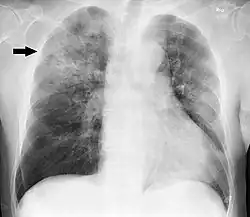

Chest X-ray of a pneumonia caused by influenza and Haemophilus influenzae, with patchy consolidations, mainly in the right upper lobe (arrow) | |